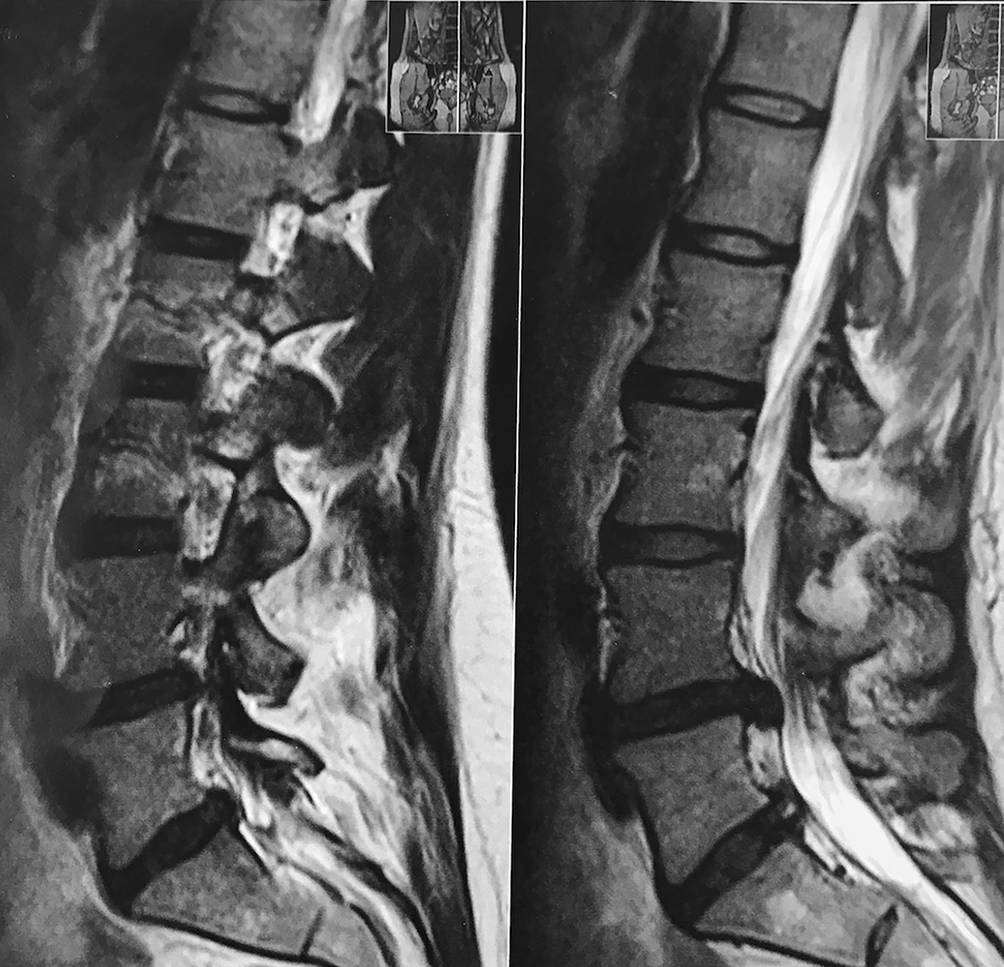

Im Sommer des vorigen Jahres traten die Schmerzen vermehrt auf und zeigten sich zunehmend therapierefraktär. Eine Nervenwurzelblockade führte zwar zu kurzfristiger Linderung, allerdings folgte wenige Tage später eine massive Schmerzverstärkung. Eine stationäre Aufnahme war die Folge, wobei eine MRT einen Prolaps L4/L5 bzw. L5/S1 mit Nervenwurzelbedrängung L5 bestätigte (Abb. 1). Die Patientin erhielt orale und parenterale Schmerztherapien, lehnte jedoch eine operative Intervention ab.

Abb. 1

Bildgebendes Verfahren (MRT) der Patientin mit den erkennbaren strukturellen Veränderungen bei intaktem posteriorem Längsband. a Sagittalschnitt MRT-Aufnahme lumbale Wirbelsäule, b Sagittalschnitt MRT-Aufnahme lumbale Wirbelsäule mit erkennbarem Diskusprolaps L4/L5 und L5/S1 bei intaktem posteriorem Längsband. (© Taxer)